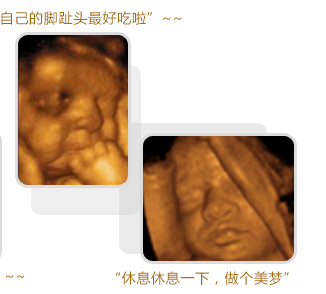

四維彩超圖

盛興醫(yī)院超聲科醫(yī)生介紹說,四維彩超就像是一個宮內(nèi)的攝影機(jī)。能為胎兒拍較為生動的“寫真”。寶寶翻跟斗、捏鼻子,各種可愛的動作四維彩超都能幫您記錄下來。不僅如此,四維彩超能夠多方位、多角度地觀察宮內(nèi)胎兒的生長發(fā)育情況,為早期診斷胎兒先天性體表畸形和先天性心臟疾病提供準(zhǔn)確的科學(xué)依據(jù)。過去的B超設(shè)備只能檢查胎兒的生理指標(biāo),而四維彩超還能對胎兒的體表進(jìn)行檢查,如唇裂,骨骼發(fā)育不良等,以便盡早的進(jìn)行治療。推選閱讀 四維彩超排畸檢查什么時候做較好